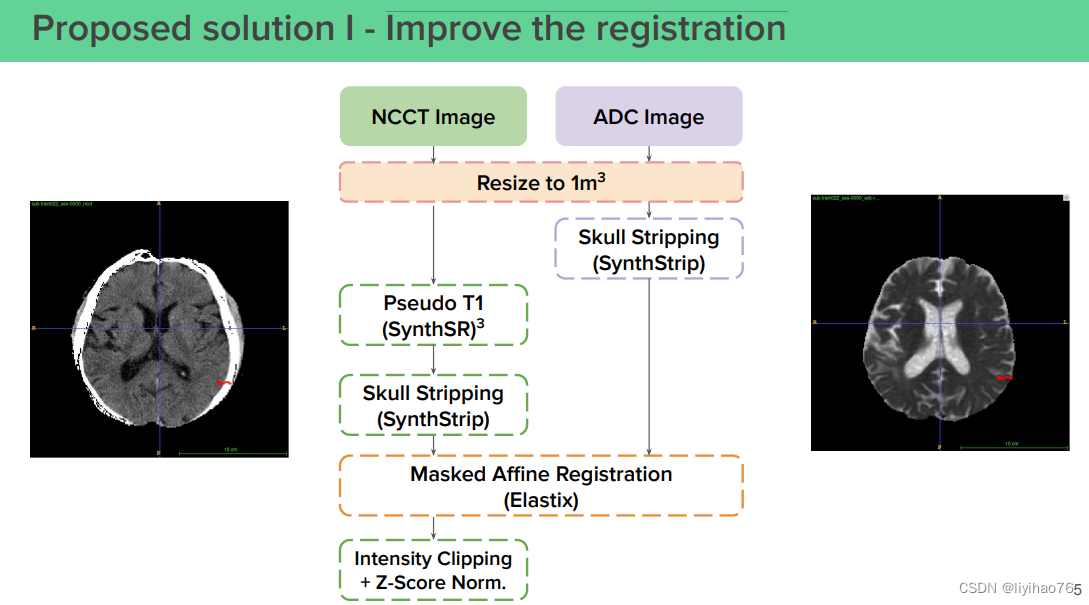

(0) 优化配准